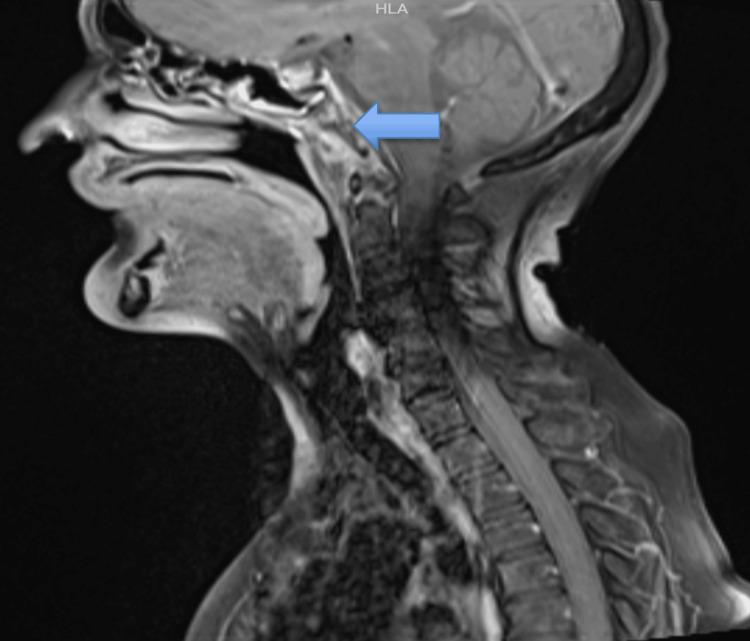

Collet-Sicard syndrome, resulting from the involvement of all four lower cranial nerves, is an extremely rare condition. This case report details a 69-year-old female patient who presented with classic signs and symptoms of lower cranial nerve palsies (IX, X, XI, and XII) and was subsequently diagnosed with Collet-Sicard syndrome secondary to tuberculosis at the base of the skull. A contrast-enhanced MRI of the neck revealed bone marrow edema in the clivus, occipital condyle, and C1 vertebra, along with diffuse surrounding soft tissue swelling and collection, findings consistent with tuberculosis. The patient was treated with antitubercular therapy and steroids, along with neuromuscular and vocal rehabilitation. She showed significant improvement two months after starting antitubercular therapy and steroids. Tubercular Collet-Sicard syndrome should be suspected in patients presenting with cranial nerve palsies, elevated erythrocyte sedimentation rate, and abnormal imaging, as early recognition and treatment can lead to successful recovery.

科莱-西卡尔综合征是一种极为罕见的疾病,由所有四条低位颅神经受累所致。本病例报告详细介绍了一名69岁女性患者,她出现了低位颅神经麻痹(IX、X、XI和XII)的典型症状和体征,随后被诊断为继发于颅底结核的科莱-西卡尔综合征。颈部增强MRI显示斜坡、枕髁和C1椎体骨髓水肿,伴有周围弥漫性软组织肿胀和积液,这些表现与结核相符。患者接受了抗结核治疗、类固醇治疗,以及神经肌肉和嗓音康复治疗。在开始抗结核治疗和使用类固醇两个月后,她有了显著改善。对于出现颅神经麻痹、红细胞沉降率升高和影像学异常的患者,应怀疑结核性科莱-西卡尔综合征,因为早期识别和治疗可实现成功康复。